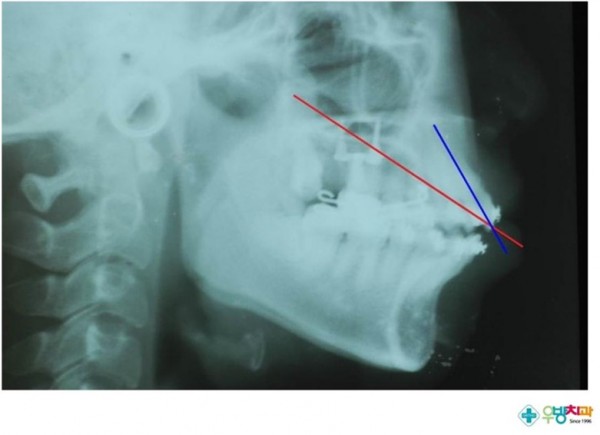

3DKP 사용자 원장님의 질문입니다.[Gummy smile, protrusion 환자 적용]